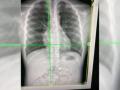

High-energy X-rays show lung vessels altered by Covid-19

London, Nov 5 Using high-energy X-rays, scientists have found how Covid-19 damages even the smallest blood vessels in ... ...